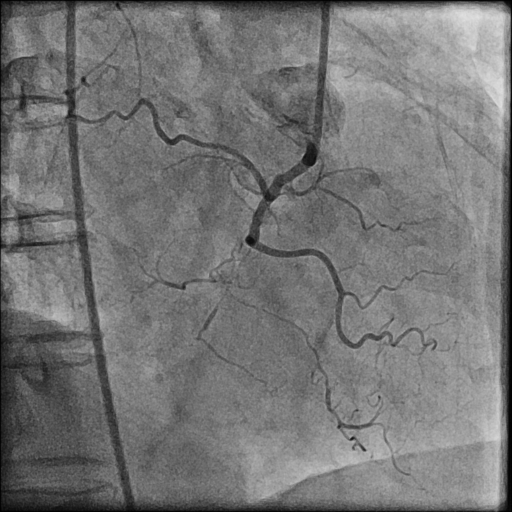

LMCA was engaged with JL 4.0 7 Fr. catheter. First septal collateral was used to reach the distal cap of the lesion using Sion black, Runthrough extrafloppy and Fielder XT-R wire with microcatheter but could not penetrate the distal cap. The lesion could not be crossed with Gaia second and Gladius¢ç Mongo¢ç wire. Antegrade approach was decided to a cross the lesion with Gaia second wire. Antegrade approach caused a dissection resulting in a sub intimal hematoma which extended into the Posterolateral branch. This dissection and the hematoma straightened the vessel near the distal cap. Now this straightening allowed the ASAHI Gladius¢ç Mongo¢ç wire to cross the distal cap retrogradely. The Gladius¢ç Mongo¢ç wire could not be positioned into the true lumen. Now to avoid further dissection proximally the Mongo wire was exchanged with Pilot 150 wire. This wire could cross the proximal cap and finally into the guide catheter. Pilot 150 wire was exchanged with Choice Floppy LS 300 cm which was externalized. A finecross microcatheter was advanced over this wire antegradely. Retrograde microcatheter removed and rest of the case was completed via antegrade approach over Runthrough NS Floppy wire. Lesion was predilated with 2.5x12 mm NC balloon @ 12 atm. Promus Elite 2.75x38 mm DES deployed in mid to distal RCA @ 12 atm. An overlapping stent Xience Xpedition 3.0x28 mm DES deployed from ostium to mid RCA @ 11 atm. Post dilatation with 3.25x10 mm NC balloon @ 11 atm. Distal TIMI III flow achieved.

Case Summary